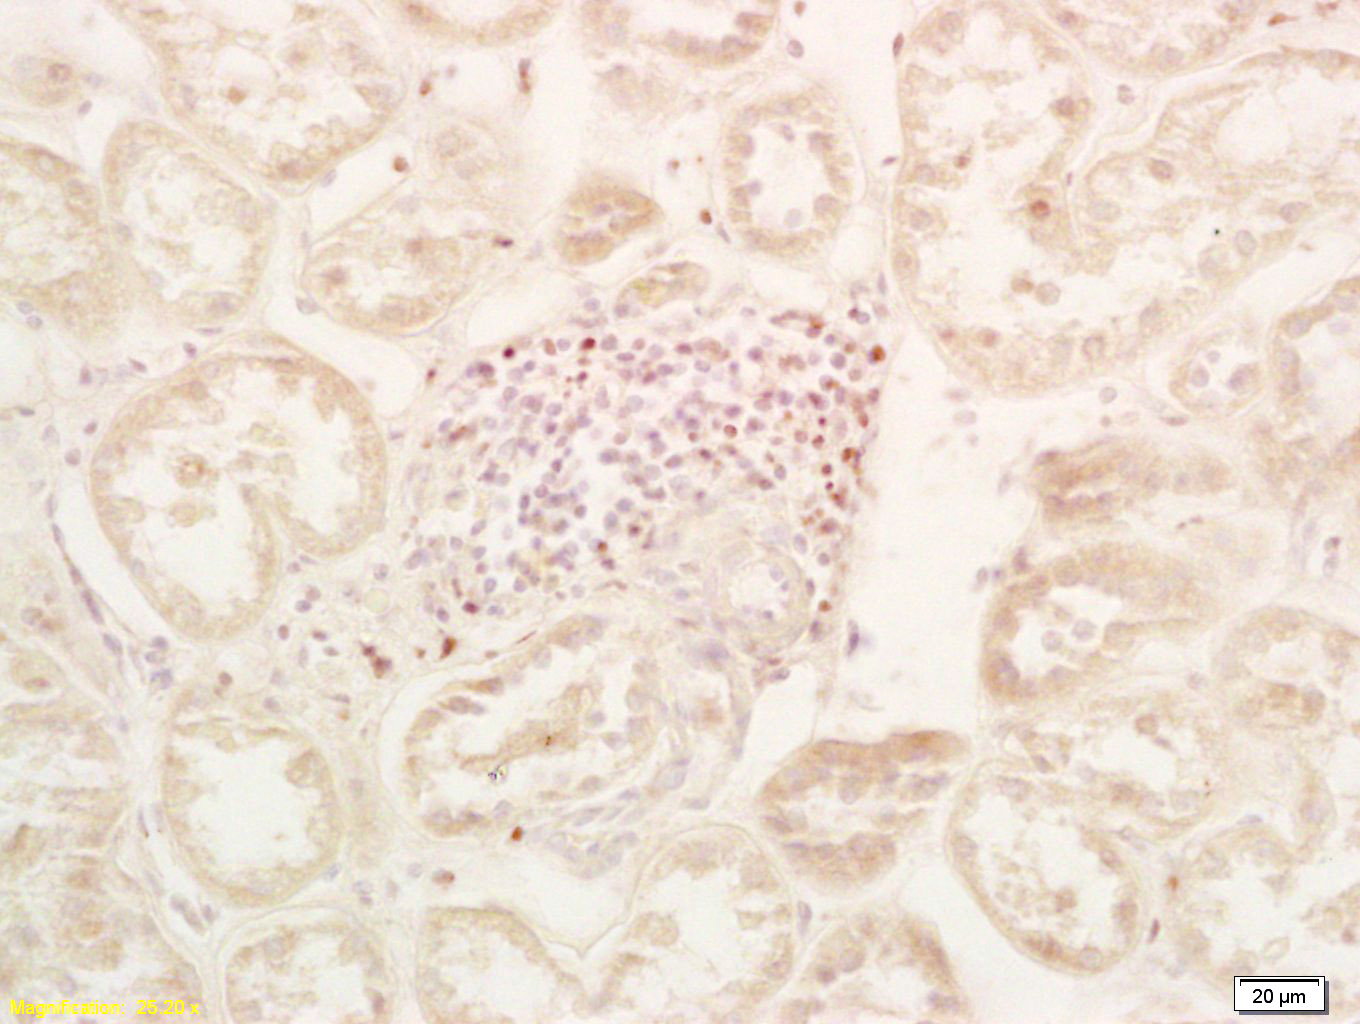

Tissue/cell: Human kidney; 4% Paraformaldehyde-fixed and paraffin-embedded; Antigen retrieval: citrate buffer ( 0.01M, pH 6.0 ), Boiling bathing for 15min; Block endogenous peroxidase by 3% Hydrogen peroxide for 30min; Blocking buffer (normal goat serum,C-0005) at 37℃ for 20 min; Incubation: Anti-PHD2 Polyclonal Antibody, Unconjugated(bs-3686R) 1:200, overnight at 4°C, followed by conjugation to the secondary antibody(SP-0023) and DAB(C-0010) staining